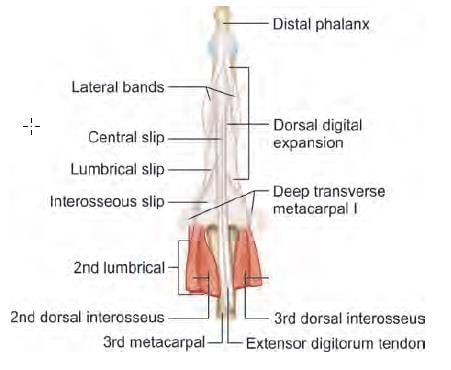

Choose the CORRECT matching pair for axillary lymph nodes in the given diagram: (INI-CET Nov 2022)